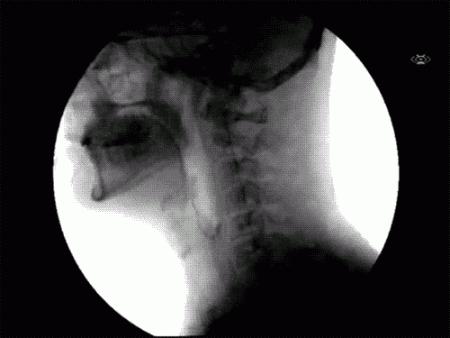

透视人类吞咽的生理过程